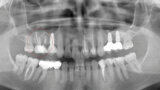

Digitální workflow a aplikace PRF a ozonové terapie v orální rehabilitaci